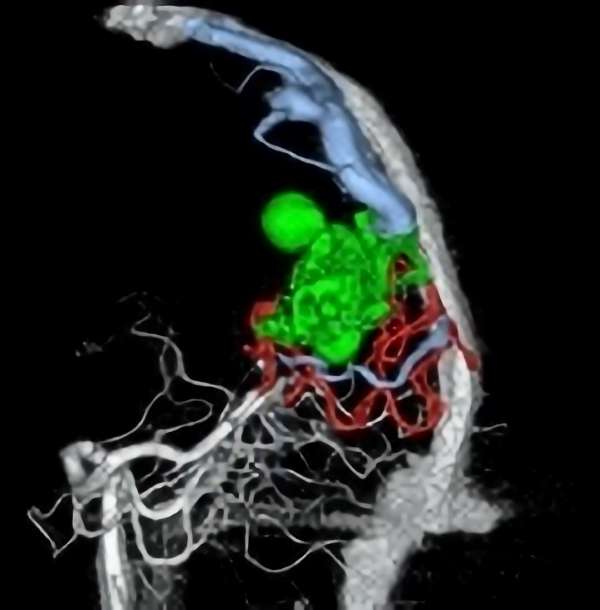

'19年5月

右中小脳脚 出血再発

SM 3(S1,E1,V1)

米国の病院

No.359 モニタリング

No.359 手術前

No.359 手術中

No.359 手術後

出血既往があり。2回の手術前血管内手術の後に、

Lateral transpeduncular approachにより再々出血予防を目的に

摘出手術を行う。完全摘出であることを確認した。

手術による合併症や後遺症なしで退院した。経過良好。